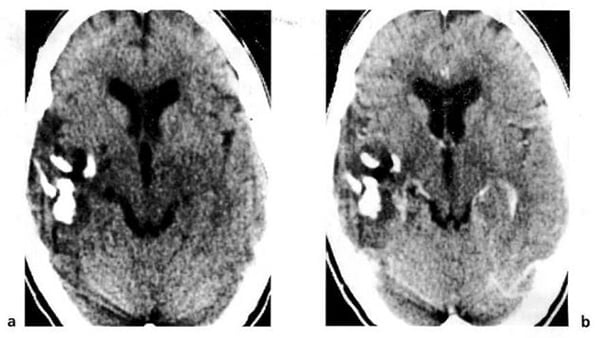

Hình 1.32. U nguyên bào đệm đa dạng. Hình ảnh trước tiêm (a) là tổn thương mật độ thấp ở hai bên đường giữa. Ở thùy trán bên trái còn có một tổn thương mật độ cao (xuất huyết). Sau tiêm (b), bắt chất cản quang mạnh, dạng viền.